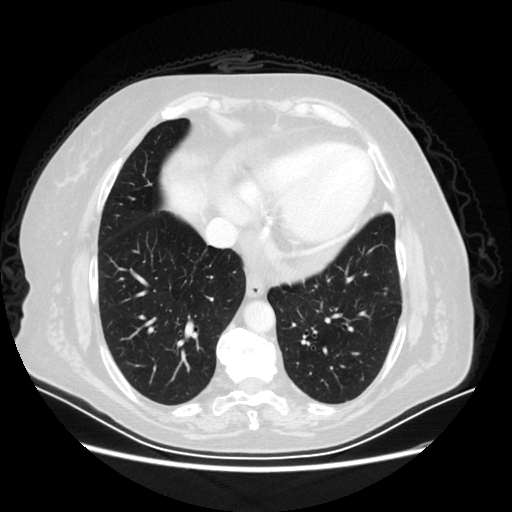

Targeted Slice 70 - Lung Window Analysis (Generated vs Real Venous)

0.633

Lung SSIM

140.5

Lung RMSE

104.3

Lung MAE

Average Lung Window Metrics Across All Slices (101 slices) - Generated vs Real Venous

0.620

Lung SSIM (Avg)

134.9

Lung RMSE (Avg)

104.4

Lung MAE (Avg)

Original VENOUS CT scan

Lung window (WL -600, WW 1500 β†’ Low βˆ’1350, High +150)